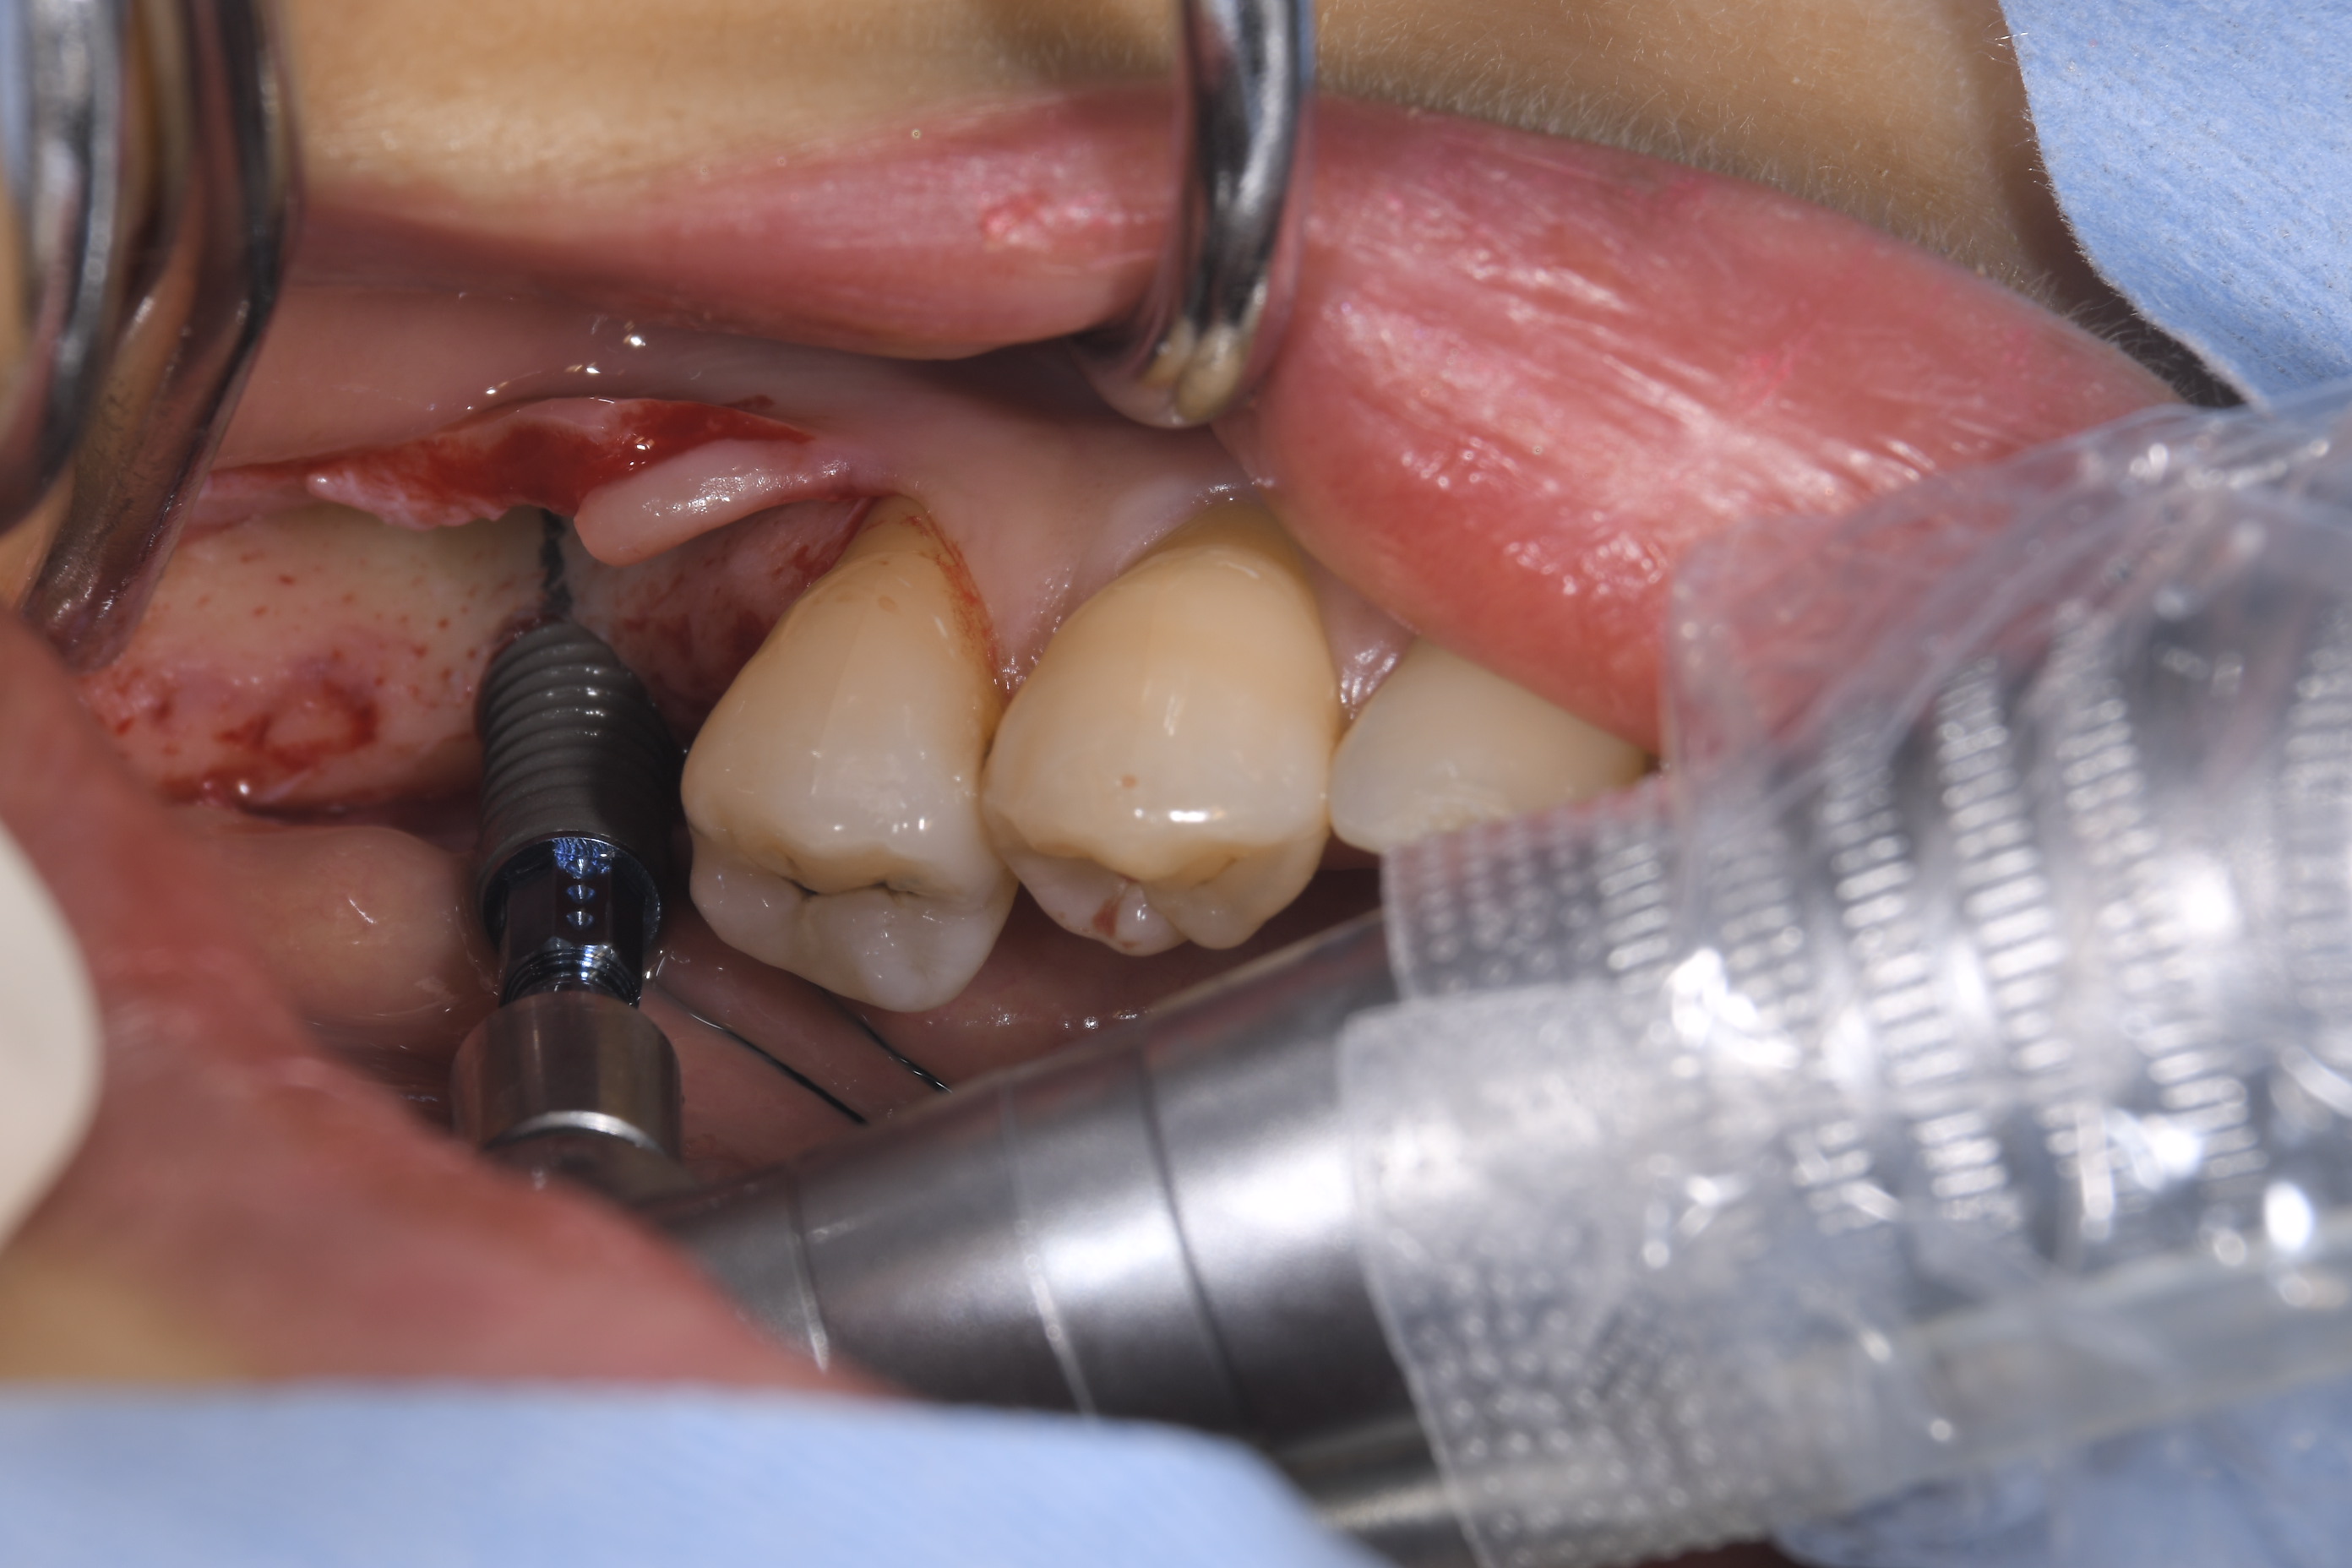

左下の6番部位にストローマンSLActiveロキソリッド4.1Φ12mmを埋入しました。

大臼歯の単独補綴で咬合力がかなりかかる部位ですが、チタンジルコニア合金素材のロキソリッドであれば問題ないと思います。

使用した、ストローマンボーンレベルインプラントSLActiveロキソリッド RC4,1Φ12mmです。